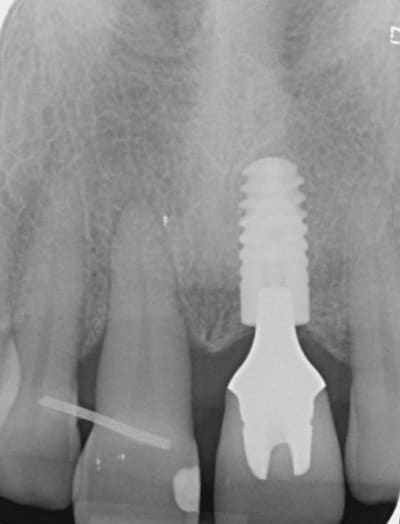

Merci jt2000, seespan et inset pour votre aide. Voici finalement le dispositif que l'on a choisi car je voulais me servir de l'implant comme ancrage.

je vous montrerai l'evolution, favorable ou.... défavorable.

je suis a l'écoute des ortho pour leurs conseils et critiques...

A virskn - Eugenol

B c15bbz - Eugenol

C abqhrm - Eugenol